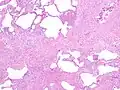

The histologic hallmarks of UIP, as seen in lung tissue under a microscope by a pathologist, are interstitial fibrosis in a "patchwork pattern", honeycomb change and fibroblast foci (see images below).[6] [7]